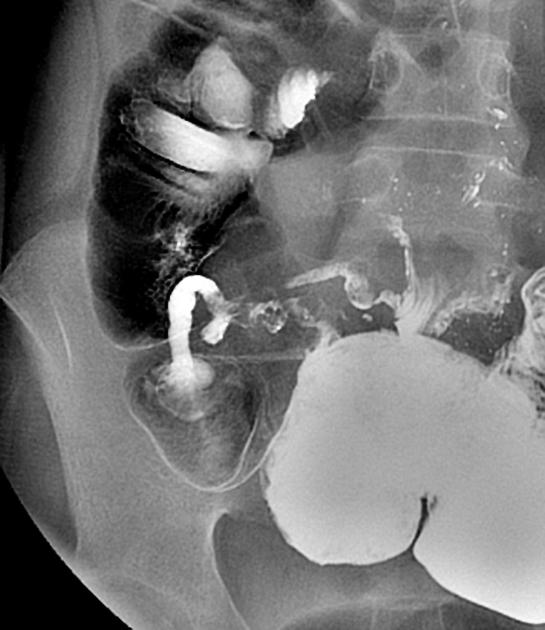

- Image de diverticulite des

diverticules du colon sigmoide et colon descendant .

Image radiologique de lavement baryte mono de

contrast |

Diverticulose colique : Les

diverticules a difference taille s'etendue le long

du colon sigmoide , colon descendant et colon

transverse ( fleche rouge ) Image en spastique du

colon sigmoide ( fleche jaune ) peu se voyait

nettete . Image lavemevt baryte mono de contrast . |